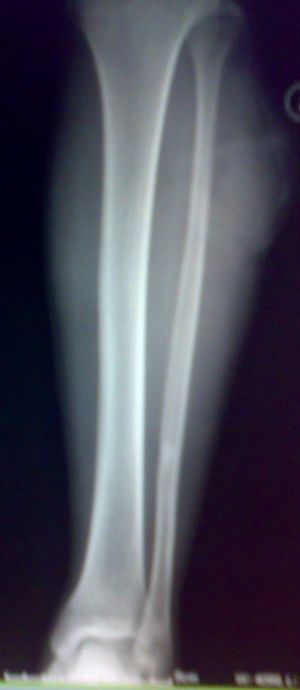

标题: X7846:M 20岁 外伤来诊。良性骨肿瘤吗?

局限性骨皮质缺损愈合修复后改变。

考虑腓骨下段良性骨肿瘤或骨肿瘤样病变(软骨瘤?);建议行mri检查。

我考虑是非骨化性纤维瘤愈合期。

考虑为腓骨内髓质型的nof。

腓骨中下段骨皮质下不规则高密度影,侧位呈水滴形。外伤,估计平时没有症状,结合病人年龄,支持纤维性骨皮质缺损

怎么那么人考虑“局限性骨皮质缺损愈合修复后改变”呢?再说骨外膜成骨较内膜成骨多见。我觉得只是一种“骨纤维构不良”或只是“骨岛”。没多大意义。